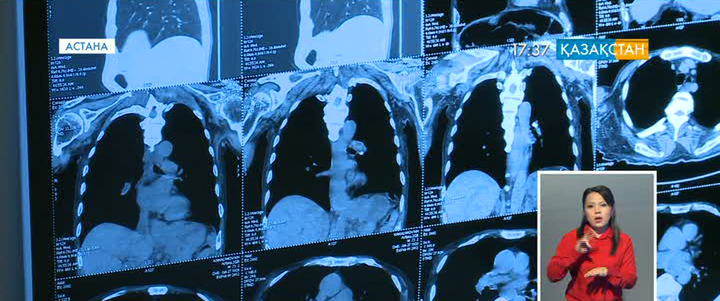

Елімізде 144 мың адам қатерлі дертке шалдыққан. Оның көбі сүт безі, өкпе және асқазан обырымен ауыратын науқастар. Соңғы кездері, әсіресе, ас қорыту органдарының обыры көбейіп барады.

Қатерлі дерттің алдын қалай алуға болады, онымен күресудің жолдары қандай деген сұрақтар бүгін халықаралық ғылыми конференцияда талқыланды.